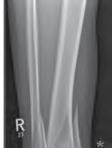

poprzeczne, spiralne, skośne, w kształcie motyla, wieloodłamowe.

Dalszy podział jest specyficzny wyłącznie dla kości rosnących i dotyczy tzw. złamań nasadowych. Został opublikowany przez Saltera i Harrisa i jest to najważniejszy podział złamań kości rosnących (ryc. 6.3 A–G).

Przebieg szczeliny złamania: A – złamanie poprzeczne (RTG, widok z przodu); B – złamanie skośne (RTG, widok z przodu i z boku); C – złamanie spiralne (RTG, widok z przodu i z boku); D – złamanie w kształcie motyla (RTG, widok z boku); E – złamanie wieloodłamowe (RTG, widok z przodu i z boku).